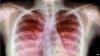

Kronik Akciğer Hastalığı Nedir? Erken doğan her çocukta olur mu?

Yenidoğanın Kronik Akciğer Hastalığı (Bronkopulmoner displazi) doğumdan sonra bebeğin oksijen ihtiyacının son adet tarihine göre 36. haftadan sonra devam etmesi olarak tanımlanmaktadır. Kronik akciğer hastalığı gelişme sıklığı <1000 gr doğan bebeklerde % 30, 501- 750 gr doğan bebeklerde ise %52 dolaylarındadır.